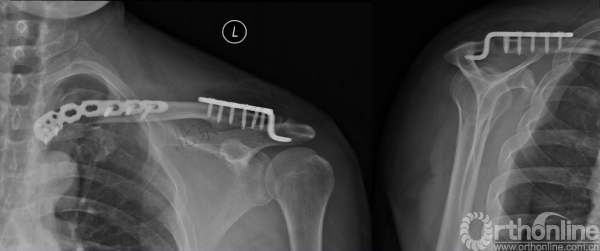

复位与固定——肩锁关节(锁骨钩板)

术中透视

复位与固定——胸锁关节

复位与固定——胸锁关节(对侧锁骨远端解剖板塑形)

术后复查(肩关节正位及出口位)